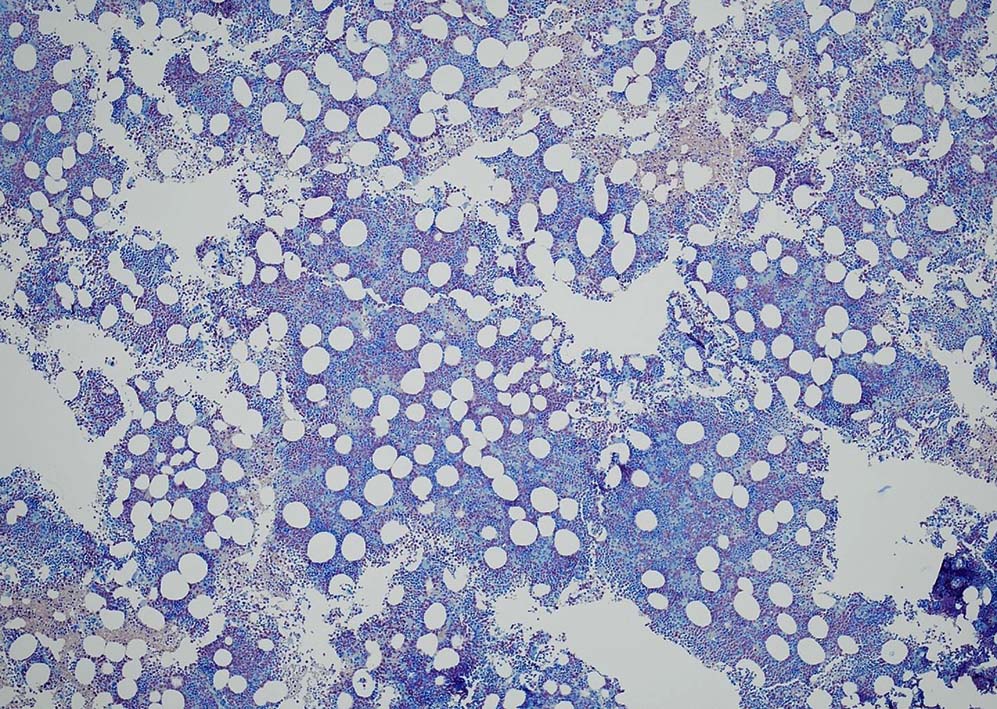

Megakaryopoiesis; Mgkは増加している. 多数の分離円形核巨核球が出現している. microMgkが増加している.

Myelogram: M/E = 1.77,Blast-M 5.2%, promyelo 7.0%, Myelo 11.4%, Meta 10.0%, Stab 5.4%, Seg 18.8%, Eo mature 0.6%, Ba mature 0.6% Mo 3.0%, Lympho 4.4%, Plasma 0.2 骨髄WT1 R 1.1x104